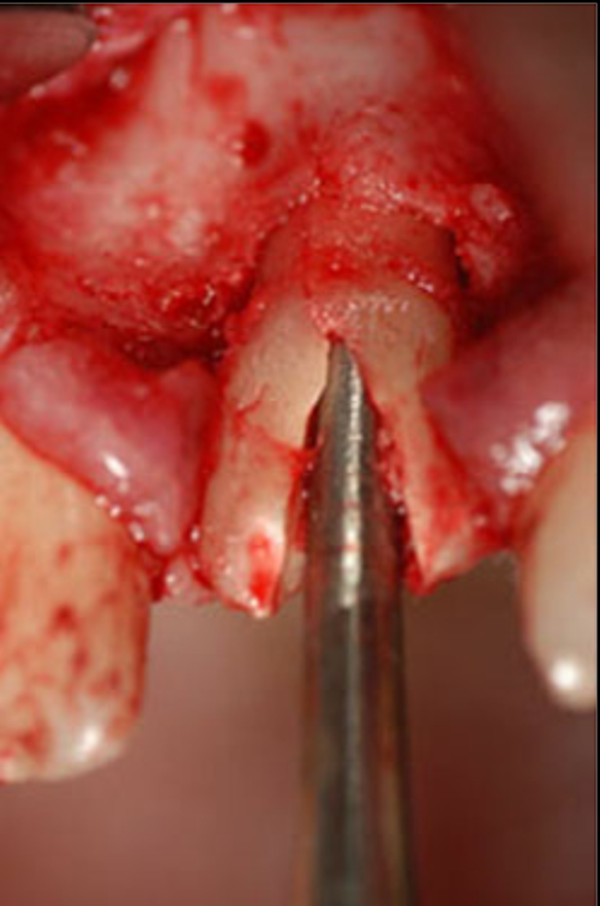

Las extracciones dentarias o EXODONCIAS, son habitualmente realizadas mediante la utilización de instrumentos denominados FÓRCEPS, los que instalados en el cuello de la pieza dentaria a extraer, son movidos de manera oscilante en el eje del diente, lográndose después de un corto período de tiempo, quitar al mismo de la cavidad ósea que lo aloja, en una operación que se denomina LUXACIÓN o AVULSIÓN. FÓRCEPS EN BOCA Esta AVULSIÓN, se produce debido a que el hueso es elástico. Sin embargo , gran parte de las veces esa elasticidad no es suficiente y se parte o rompe la «corteza ósea» que rodea al diente, en su región más cercana a la «zona cortante» del mismo.Esa ruptura o fractura, es favorecida por el uso de los Fórceps, dado que sus «mordientes» se sitúan muy cerca de del hueso. .FÓRCEPS ROMPIENDO LA TABLA TABLA ROTA La idea de crear un instrumento que impida dicha fractura, se basa en la certeza de que cuanto más adentro del diente, y cuanto más cerca de la punta del diente, se efectúe la fuerza de AVULSIÓN, menos posibilidades de fractura existirán por una simple cuestión de física básica: CUANTO MÁS LARGO SEA EL BRAZO DE POTENCIA DE UNA PALANCA, MENOS ACCIÓN TENDRA EL BRAZO DE RESISTENCIA….POR LO TANTO SERÁ NECESARIA MENOS POTENCIA PARA VENCER LA RESISTENCIA… O SEA, CON MOVIMIENTOS MAS DELICADOS , LOGRAREMOS EL MISMO EFECTO. ESQUEMA DE DIENTE MOSTRANDO LA ACCIÓN DE LAS FUERZAS DE UN FÓRCEPS. ESQUEMA DE DIENTE MOSTRANDO LA ACCIÓN DE FUERZAS DE UN AIDA Cuando la especialidad IMPLANTOLOGÍA, no se había desarrollado tal como ahora la conocemos, la fractura de esa «corteza ósea» denominada TABLA EXTERNA O INTERNA del PROCESO ALVEOLAR, carecía de importancia ya que la cicatrización se produce irremediablemente en ausencia de infecciones Sin embargo, a la luz de los conocimientos actuales, la preservación de dichas TABLAS, son de capital importancia para la realización de un IMPLANTE INMEDIATO(Implante colocado en el mismo acto quirúrgico que la extracción), y para el logro de su INTEGRACIÓN Y ESTÉTICA futura. Es por eso que exponemos ante las autoridades competentes, la idea de patentar un instrumento como el que denomino: AVULSIONADOR INTRADENTARIO ATRAUMÁTICO …cuyas características principales son: MATERIAL: ACERO QUIRÚRGICO 316 LONGITUD TOTAL:13 mm PUNTA ACTIVA: 6 mm FORMA DE PUNTA ACTIVA: HELICOIDAL DECRECIENTE DOS GROSORES DE PUNTA. INSTRUMENTO AD HOC Por acción de las espiras , el instrumento se fija en las paredes del canal dentario, produciendo un anclaje que permite la AVULSIÓN. CRESTA ÓSEA COMPLETAMENTE CONSERVADA